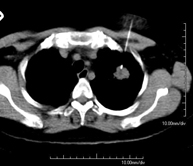

- CT-guided thoracic FNA (fine needle aspiration)

This test obtains a sample of tissue from thoracic lesions, such as lung masses, mediastinal masses, bone lesions, etc. This test is performed using local anaesthesia on the puncture area, which is administered with fine-gauge needles. The entire procedure is performed with guidance from images obtained by computed tomography (CT) at various stages of the puncture, using fluoroscopy-CT equipment. After the test, the patient remains in hospital for a few hours. Coagulation tests must be performed before the puncture.